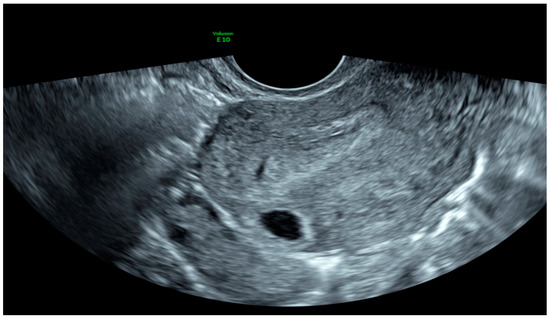

| Case 1 | Asymptomatic | 12 + 1 | 97,388 | GS 78 × 60 mm; with embryo | Radical surgical treatment (LPS hysterectomy + bilateral salpingectomy + uterine arterial embolization + bilateral ureteral stent placement) | Complete resolution |

| Case 2 | Asymptomatic | 6 + 6 | 10,862 | GS 20 × 19 mm; with embryo | Hys: 1st step: CP resection by twizzle; IC Foley catheter 2nd step: vessels electrocoagulation by bipolar twizzle | Reoperation (hys) due to tissue residues and cervical laceration Complete resolution |

| Case 3 | Asymptomatic | 5 | 9747 | GS 20 × 22 mm; no embryo | MTX IM 50 mg/m2 of body surface + Hys | Complete resolution Currently pregnant (PMA Homologous) |

| Case 4 | Brownish vaginal discharge | 6 + 6 | 55,951 | GS 30 × 10 mm; no embryo | Hys | Complete resolution |

| Case 5 | Vaginal bleeding | 9 | 1331 | GS 4.7 × 5 mm; no embryo | Mifepristone 600 mg orally + Misoprostol 400 mcg + MTX IM 50 mg/m2 of body surface | Complete resolution |

| Case 6 | Vaginal bleeding | 6 | 4274 | GS 5.4 × 5 mm with embryo | MTX IM 50 mg/m2 of body surface + Hys: CP resection by twizzle | Complete resolution |